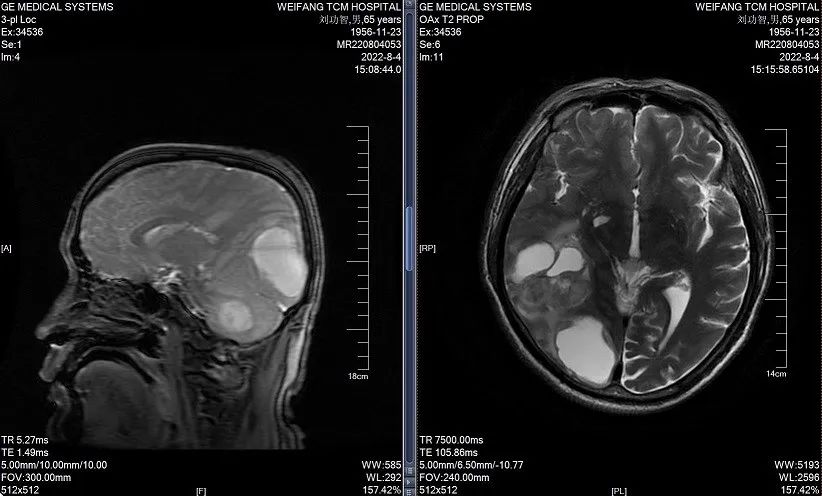

2023年3月21日(维持治疗4周期后)颅脑MRI:右侧小脑半球、右侧颞、枕叶及双侧侧脑室旁、右侧半卵圆中心多发异常信号,对比2023.01.02号片右侧小脑半球、右侧颞叶病灶有减小。

图5.治疗后颅脑MRI

图6.维持治疗后颅脑MRI